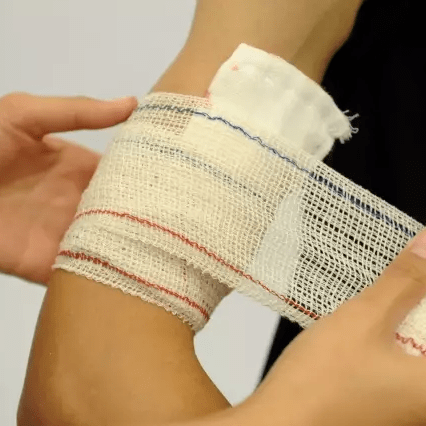

近距离受伤的手臂包裹在弹性绷带

图片尺寸1200x821